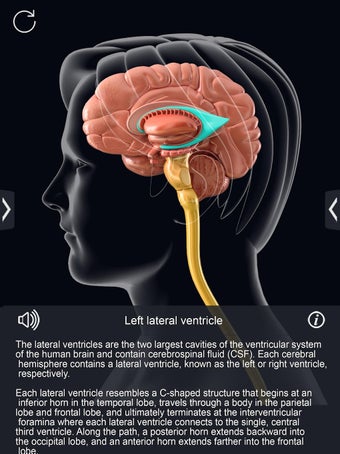

برنامج تشريح الدماغ Pro هو تطبيق تعليمي لدراسة تشريح الدماغ البشري. تم تصميم هذا التطبيق لكل من الطلاب الطبيين والجمهور العام. يتيح للمستخدمين استكشاف الدماغ من جميع الزوايا وعرض التشريح بطرق مختلفة. إنه أداة سهلة الاستخدام تتيح للمستخدمين تدوير 360 درجة والتكبير والتصغير وتحريك الكاميرا حول نموذج ثلاثي الأبعاد واقعي للغاية. يتيح للمستخدمين القدرة على تحديد الأجزاء وعرضها بالأشعة السينية وإخفائها وإظهارها وعرض الرسوم المتحركة في الوقت الحقيقي والرسم أو الكتابة على الشاشة ومشاركة لقطات الشاشة ونطق الصوت لجميع مصطلحات التشريح والمزيد. إنه تطبيق تعليمي مجاني.